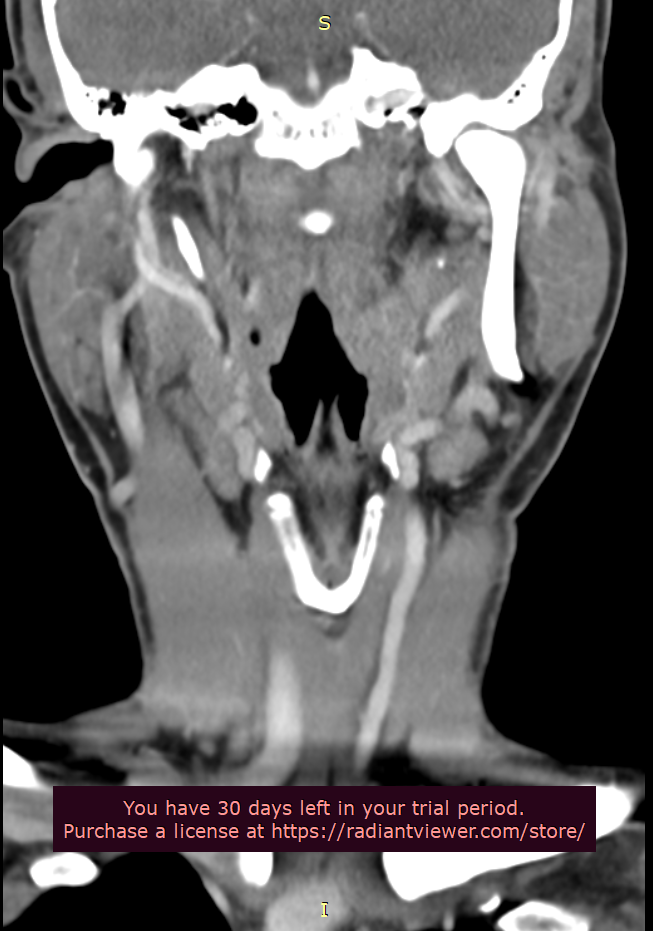

Please do a CT VENOGRAM of the brain and cervical spine with contrast. Please do a 3D reconstruction to show styloids. Please also measure the styloids.

Patient with symptoms of intracranial hypertension (pseudotumor cerebri) compatible with compression of the internal jugular vein at the transverse process of atlas (C1) or styloid process. Please do the scan in neutral.

Please make sure the CT Scan is capture while the contrast is in the internal jugular vein. This patient is suspected of having significant compression of the internal jugular vein(s) between the styloid bone and/or atlas. This is not a CT angiogram order it is a venogram. Surgical decisions will be made based on this scan.